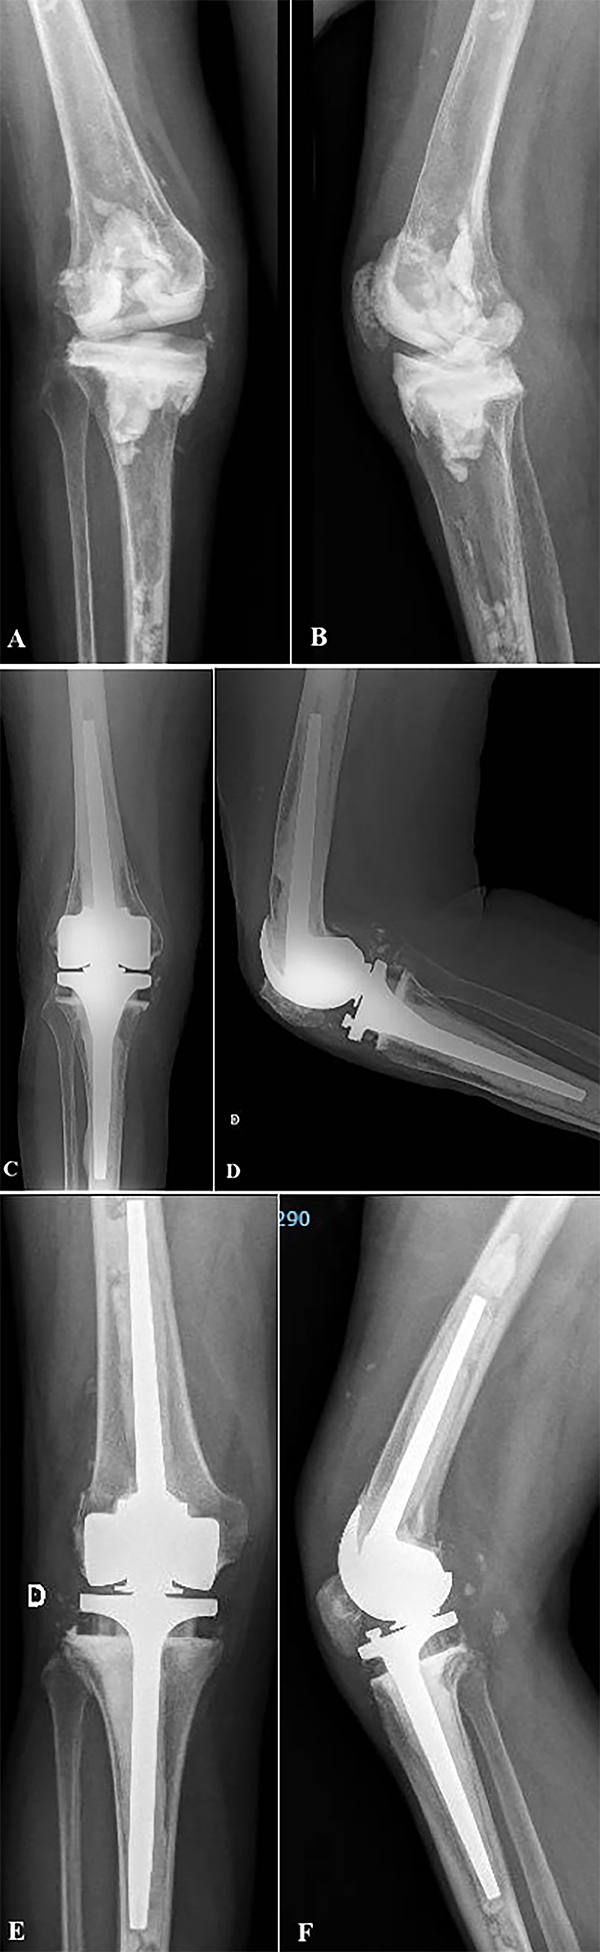

La luxación protésica por falla del mecanismo abisagrado esta descripta en la literatura con una incidencia del 2 al 10%. La ruptura del buje de polietileno, la ruptura del poste metálico o del inserto tibial por fatiga, o la ruptura del mecanismo antiluxación son causas que pueden producir esta grave complicación.14, 16, 17, 32, 34 Wang y cols. reportaron la ruptura del buje de polietileno del componente femoral de la bisagra a los cinco meses de implantar una prótesis Endo-Model;14 y otros autores, en una serie de noventa y ocho pacientes, reportaron nueve casos de ruptura del mecanismo abisagrado.33 En nuestra serie informamos dos pacientes (8%) con una luxación protésica secundaria a la ruptura del buje de polietileno del mecanismo de bisagra, un porcentaje similar al descripto en la literatura (fig. 5). Ambos casos ocurrieron con la utilización del mismo tipo de implante (Rotax, FII SA®, Saint-Just-Malmont, Francia), lo que representa el 50% de los pacientes con dicho implante de nuestra serie. Similar complicación con este implante fue reportada por Gómez y cols. del Hospital Británico de Buenos Aires.34

Figura 5: Caso 2. A y B) Paciente de sesenta y siete años con prótesis abisagrada Rotax, FII SA®, Saint-Just-Malmont, Francia. Radiografía de frente y perfil donde se observa una luxación posterior de rodilla. C) Imagen clínica de la luxación protésica. D) Imagen intraoperatoria donde se observa la ruptura del polietileno del componente femoral. E y F) Revisión protésica con prótesis abisagrada Endo-Model, seguimiento a los cinco años.